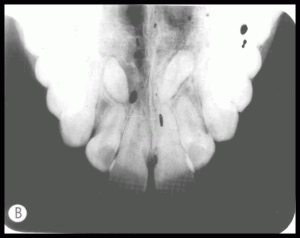

PROBLEM: HERRING BONE OR TIRE-TRACK IMAGE

CAUSE: Film placed backward and then exposed. X-ray beam attenuated

by the lead foil backing in the film packet

ACTION: Always place the white side of the film adjacent to the teeth